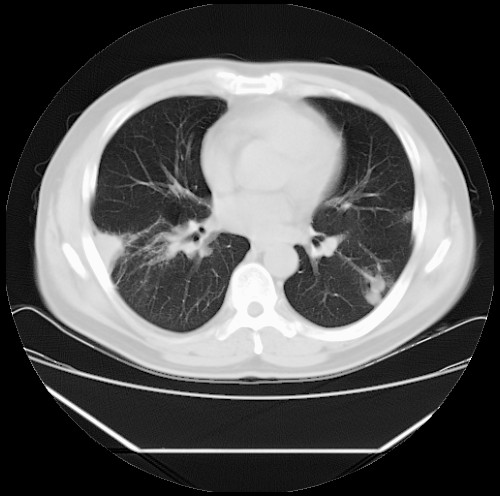

标题: CT22085:双肺多发结节

男,44岁,咳嗽,痰中带血2天。

病灶大部分位于胸膜下,结节大小相差不是很大,肺尖太干净。这种结核没见过,我认为可排除。

除肺内及胸膜下可见多发大结节外,在肺小叶中心核、小叶间隔及支气管血管束上亦可见多方小结节,可以认为是随机分布。考虑转移可能性大。

仔细观察病灶形态,病灶边界部分清楚,结合临床症状,首先考虑转移,纵隔内多个肿大淋巴结影。

双肺血管纹理末端多发类圆形结节,边界光滑清晰 气管前腔静脉后淋巴结肿大

考虑转移瘤

沿血管分布,位于血管末端。转移瘤多见,血行性菌栓也可见到。

本例双肺多发类圆形高密度灶,边清,结合病史多考虑双肺多发转移改变,可以结合实验室检查。